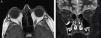

RM orbitaria: engrosamiento de los músculos extrínsecos oculares y aumento de la grasa orbitaria, con empeoramiento en segunda RM tras 3 meses (fig. 2).

Evaluación oftalmológica: exoftalmometría: ojo derecho 19mm, ojo izquierdo 18mm. Aumento de la presión intraocular del ojo izquierdo (26mmHg [11-17]). Alteración de la vía visual bilateral: retraso en la onda p100 en los potenciales evocados visuales y adelgazamiento de las fibras nasales del nervio óptico del ojo izquierdo en tomografía de coherencia óptica. Agudeza visual y campimetría normales.